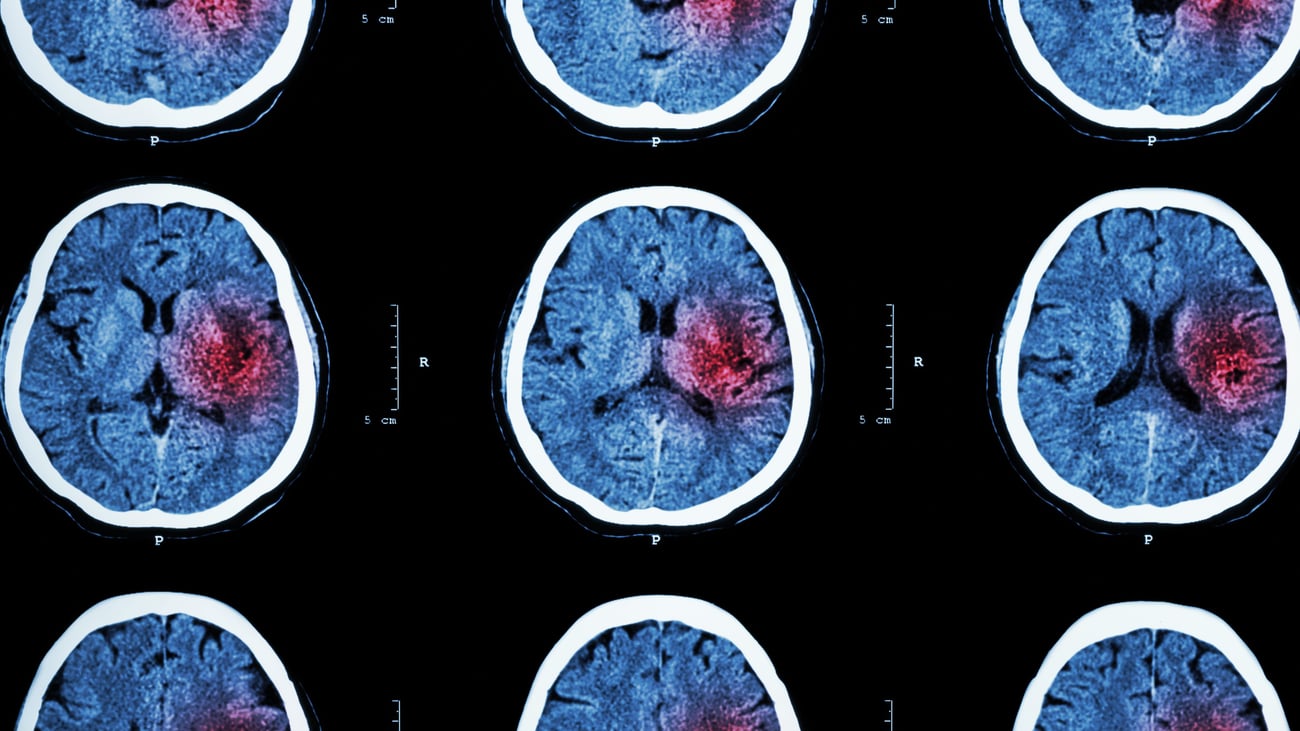

Síntomas de accidente cerebrovascular a los que debemos prestar atención: Conozca los síntomas de "BEFAST" |

Mayo es el mes de concienciación sobre el accidente cerebrovascular. El accidente cerebrovascular es un trastorno neurológico que se caracteriza por una obstrucción o interrupción del flujo sanguíneo al cerebro. Esto puede deberse a un suministro ineficiente de sangre y oxígeno al cerebro (accidente cerebrovascular isquémico) o a una hemorragia o fuga en los vasos sanguíneos (accidente cerebrovascular hemorrágico). En los Estados Unidos, el accidente cerebrovascular es la causa principal de discapacidad a largo plazo y morbilidad, y la quinta causa principal de muerte que afecta a casi 795.000 personas cada año.

Este mes, Jennifer Elloyan, enfermera registrada y directora del Programa de Accidente Cerebrovascular (Centro Integral de Accidente Cerebrovascular) comparte seis signos y síntomas de advertencia, conocidos como "BEFAST", que pueden indicar el comienzo de un accidente cerebrovascular. A continuación, encontrará una lista de verificación de lo que debe tener en cuenta si sospecha que usted o un ser querido está sufriendo un accidente cerebrovascular.

¡Rita Tarabelli, enfermera profesional, fue excepcional! Se preparó a conciencia con mi historial y fue una educadora excepcional. ¡No solo me explicó el accidente cerebrovascular para que pudiera entender mejor lo que había sucedido, sino que nos mostró un escáner cerebral para ilustrarlo! Al salir del consultorio, sentí que estaba en muy buenas manos —¡y la recomiendo ampliamente! |